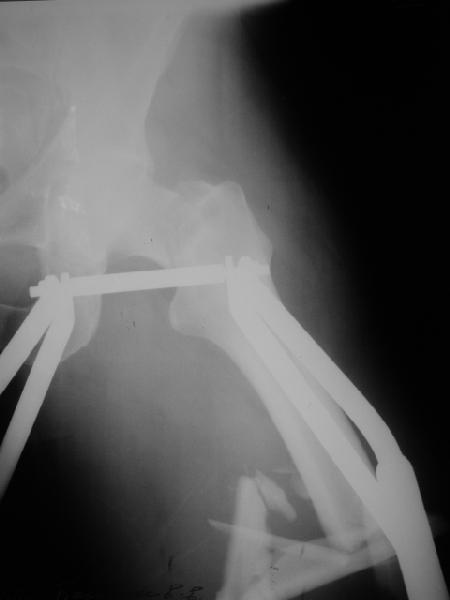

В продожение предшествующего обсуждения. В ущерб академизму для уменьшения объема кладу только одну проекцию, суть проблемы из нее ясна.

У больного 51 года в результате автоаварии 2 нед. назад перелом шейки бедра (как обычно в таких случаях, вертикальный) и открытый (прокол изнутри, ушитая по месту первичного поступления рана 2 см) многооскольчатый перелом диафиза этого же бедра. Видимо, тоже такой перелом надо кодировать как два отдельных, с плюсом, по совету проф. Лазарева?

Как лучше оперировать? От доступных вариантов глаза разбегаются - антеградный диафизарный гвоздь плюс винты в шейку бедра мимо гвоздя, реконструкционный с винтами в шейку сквозь гвоздь, гамма или проксимальный гвоздь аналогично, винты в шейку плюс гвоздь через колено; пластины и аппараты тоже доступны. На чем бы Вы остановили выбор и почему?

Recently I posted an image of ipsilateral trochanteric and spiral shaft fractures, with request to pick a most appropriate code for the injury using AO/OTA fracture classification. I receive a couple of replies from Russian ortho list with advice to code fractures separately maybe adding '+' sign. Is this approach common? Or there is another opinion about proper coding? Now same question is about ipsilateral neck and shaft fractures. A male 51 years old referred to our unit 2 weeks after a car accident with the injury. What is correct OTA/AO code for this? The shaft part was open - a puncture wound, no signs of infection. Also the patient has a right forearm fracture - both shafts, and left clavicula. There is a lot of treatment options available for the femur - antegrade shaft nail and neck screws "miss a nail", reconstruction, gamma or proximal nails, a retrograde nail and screws to the neck; plates and external fixators are also available. What and why would be best choice?